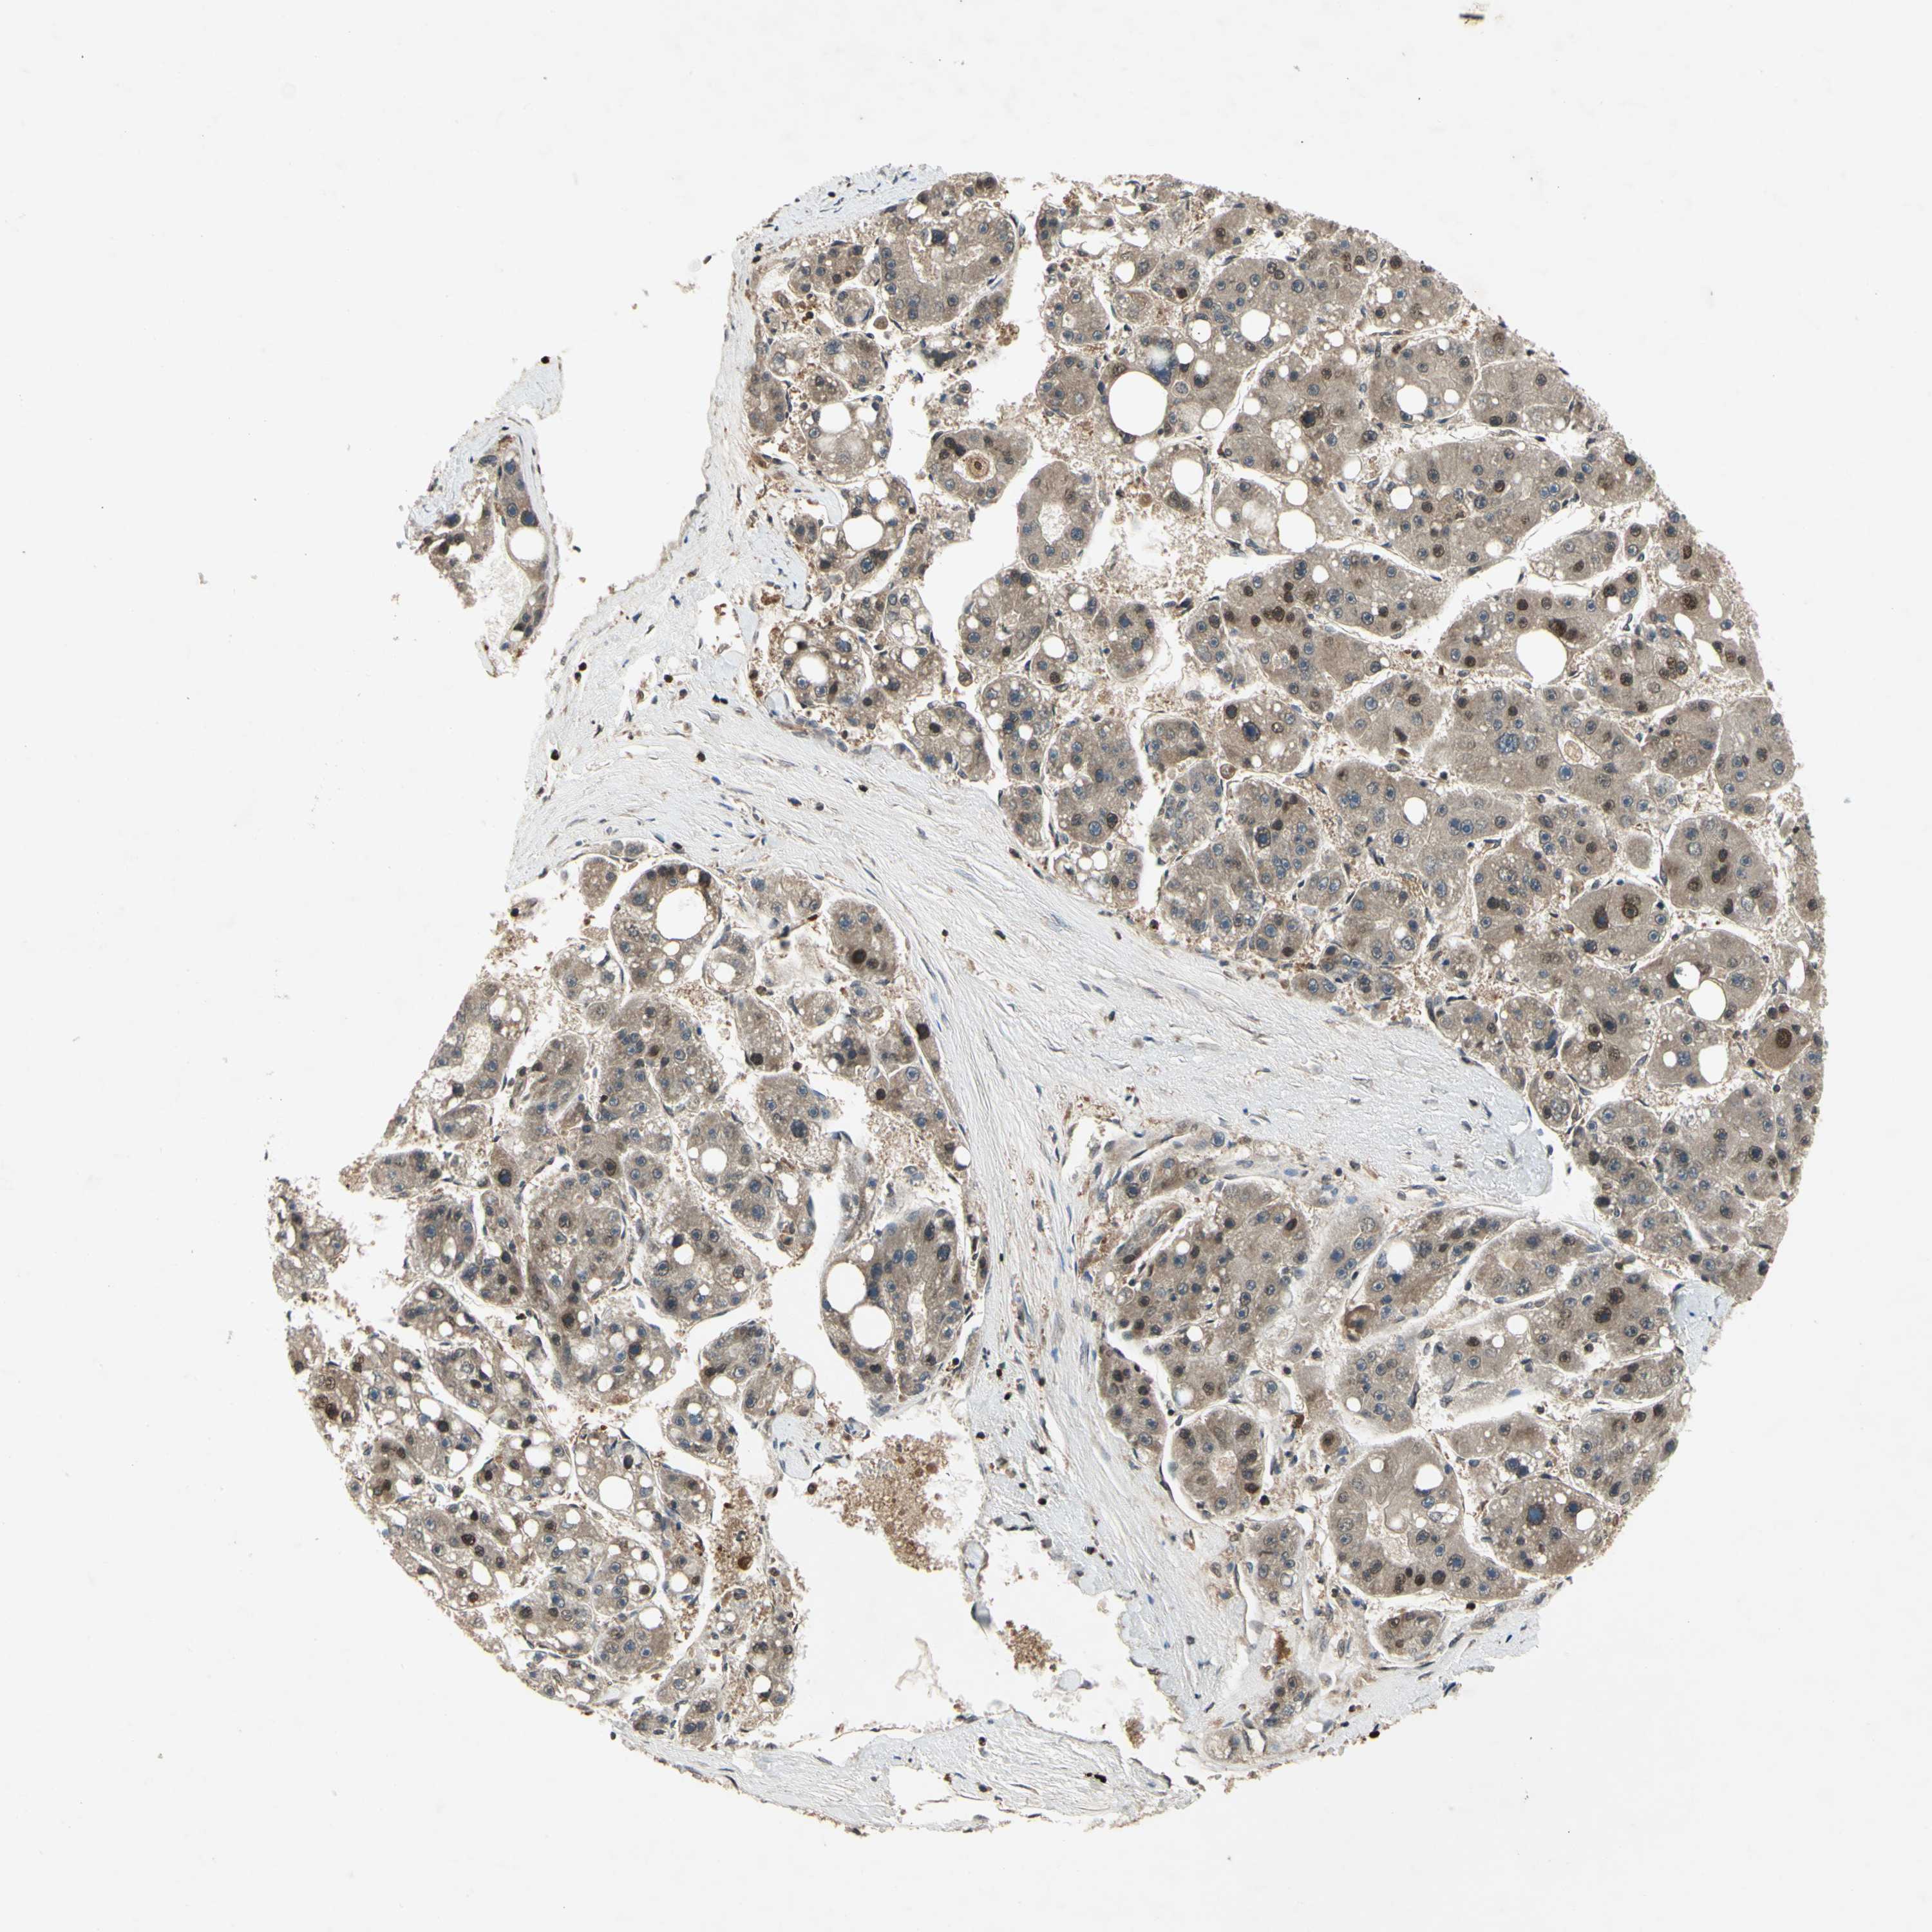

LIVER CANCER - Protein expressioni

A mouse-over function shows sample information and annotation data. Click on an image to view it in a full screen mode. Samples can be filtered based on level of antibody staining by selecting one or several of the following categories: high, medium, low and not detected. The assay and annotation is described here.

Note that samples used for immunohistochemistry by the Human Protein Atlas do not correspond to samples in the TCGA dataset.

Antibody stainingi

Antibody staining in the annotated cell types in the current human tissue is reported as not detected, low, medium, or high, based on conventional immunohistochemistry profiling in selected tissues. This score is based on the combination of the staining intensity and fraction of stained cells.

Each image is clickable and will lead to virtual microscopy that enables deeper exploration of all samples and also displays staining intensity scores, fraction scores and subcellular localization as well as patient and tissue information for each sample.

Antibody HPA001538

Antibody CAB008632

Cholangiocarcinoma

Carcinoma, Hepatocellular, NOS